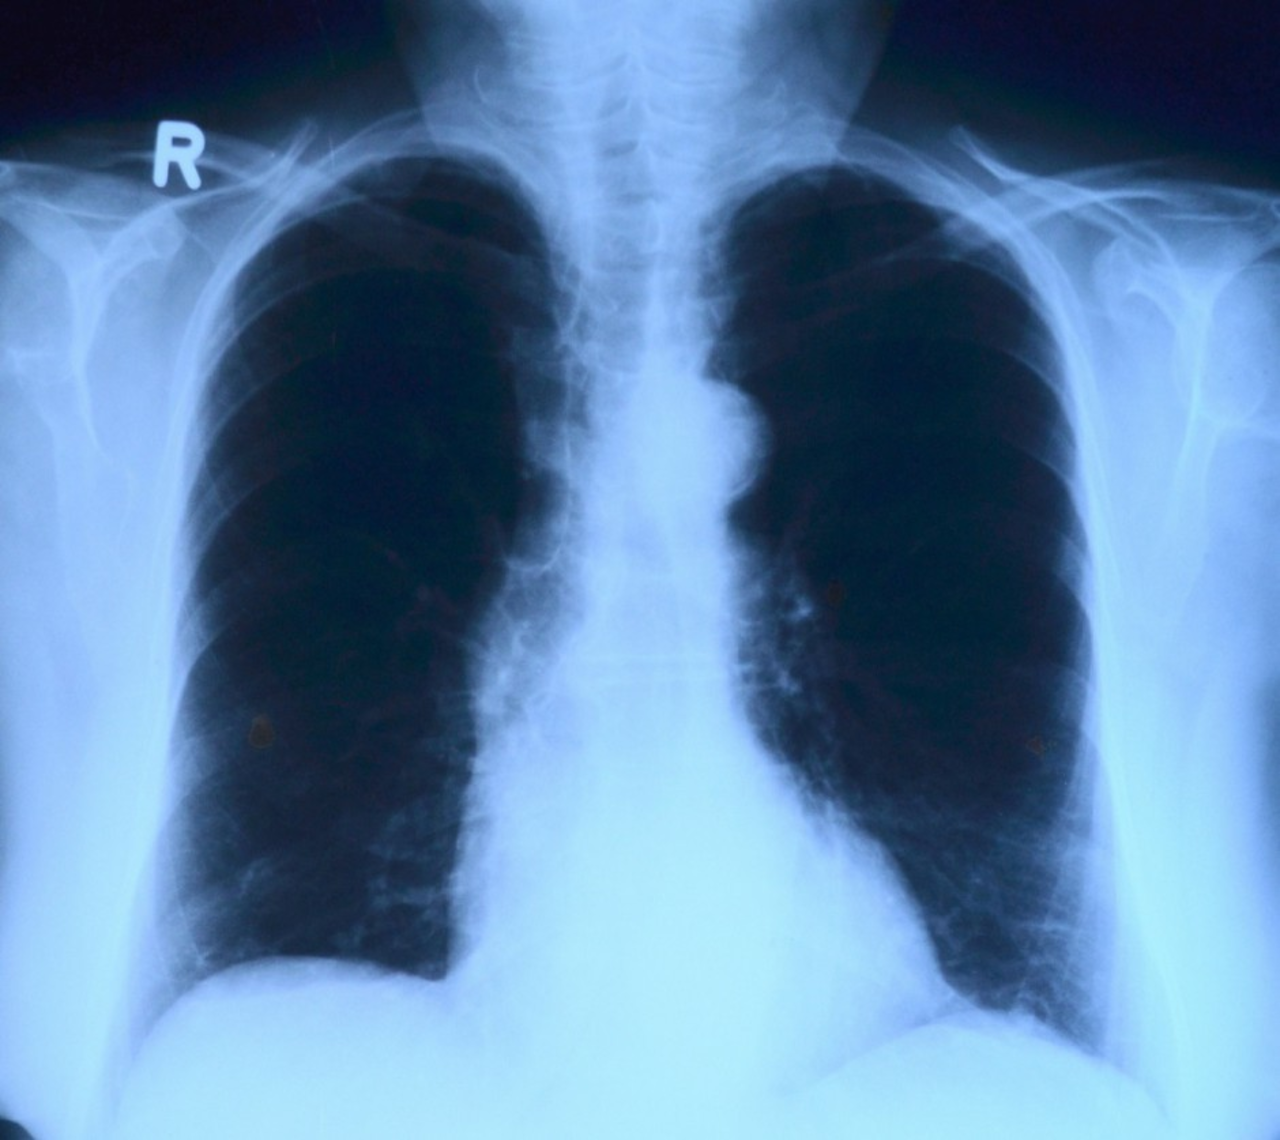

Dla wielu pacjentów zakażenie koronawirusem Sars-Cov-2 nie kończy się ustąpieniem najbardziej charakterystycznych objawów bądź zakończeniem kwarantanny. Coraz więcej pacjentów ma powikłania pocovidowe dotyczące układu oddechowego oraz szereg innych dolegliwości.

Większość osób przechodzi zakażenie koronawirusem łagodnie lub nawet bezobjawowo. Jednak nawet kilka miesięcy po przebytej infekcji niektórzy mogą zmagać się z szeregiem powikłań, wśród nich jest m.in. uszkodzenie miąższu płuc, schorzenia nerek, wątroby, zmiany skórne czy powikłania w obrębie układu sercowo-naczyniowego.

– Obecnie w swojej praktyce spotykam coraz więcej pacjentów, którzy przebyli chorobę Covid-19 i mają powikłania ogólnoustrojowe, jednak głównie ze strony układu oddechowego. Często te zmiany widać na wykonanym zdjęciu radiologicznym klatki piersiowej czy w tomografii komputerowej, ale też sami pacjenci skarżą się na duszności, ogólne osłabienie, zmniejszoną saturację krwi, temu wszystkiemu towarzyszą również  objawy kardiologiczne – mówi dr Zbigniew Bajor, pulmonolog.

– Trzeba również przyznać, że coraz więcej młodych ludzi przechodzi ciężko Covid-19 i później ma poważne powikłania. Spotykam w swojej praktyce częściej osoby młode, które przed zachorowaniem były w doskonałej kondycji fizycznej, a po przebyciu koronawirusa mają zdecydowanie gorszą wydolność organizmu i osłabienie ogólnoustrojowe – dodaje specjalista.

Infekcja Sars-Cov-2 nawet o lekkim przebiegu może prowadzić również m.in. do zapalenia mięśnia sercowego, ponadto specjaliści obserwują wzrost ryzyka zawału serca oraz zaburzenia jego rytmu. Do poważnych zagrożeń związanych z zakażeniem koronawirusem należą również powikłania zakrzepowo-zatorowe.